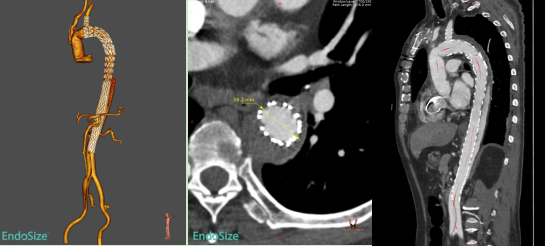

术前,胡佳主任医师团队对患者病情进行了详尽的术前评估和反复讨论,经过精细影像学分析和手术模拟推演,制定了个体化手术治疗方案。术中,患者全麻后采用左侧股动脉穿刺建立通路,主动脉造影证实象鼻支架以远残余夹层真腔狭窄,存在多发内膜破口。手术选用近端直径30mm、远端直径24mm、长度290mm的A型夹层全腔内重建系统,其中覆膜段长度为120mm。支架近端锚定于象鼻支架内,远端锚定于肾下腹主动脉。手术过程顺利流畅,术后即刻造影显示胸段残余夹层近端破口有效覆盖,近端假腔不再显影,远端真腔扩张良好,手术治疗效果达到预期。

术后复查的CTA